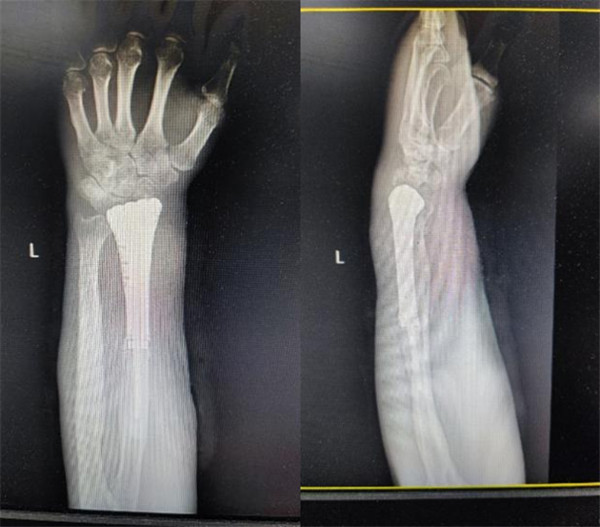

术后X线片

术前宋教授团队为患者进行个性化手术方案设计,通过CT采集患者的桡骨形态数据,用3D打印技术制作了腕关节假体,经过完善的术前规划及精细的术中操作,在骨关节外科团队和麻醉手术科的密切配合下,成功实施既定的手术方案。术后患者恢复良好,康复师循序渐进地指导其功能锻炼。出院之时,患者及其家属对王坤正教授团队表达了感激之情,感谢他们为病人保住了上肢。正所谓:妙手去病魔,仁心留全肢。